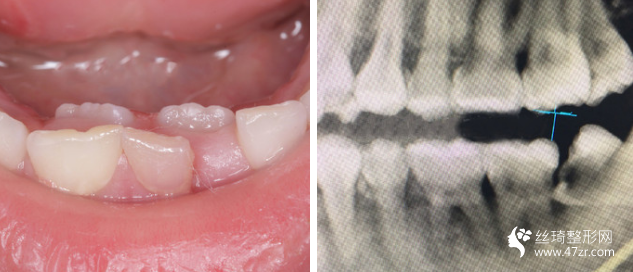

3.南京友誼整形外科醫(yī)院沈宏瑜主治醫(yī)師案例展示

一直以來(lái),我算是一個(gè)對(duì)自己要求比較高的人,見(jiàn)不得自己有任何的瑕疵,就連牙齒也不行。 所以在我開(kāi)啟牙齒矯正路途前的三個(gè)月里,我托了較為多人進(jìn)行行業(yè)摸底

我的牙齒其實(shí)問(wèn)題不大,但是下面兩個(gè)牙齒被擠的歪了出來(lái),而且我 一直覺(jué)得我的嘴有點(diǎn)往外凸出,所以一直都有矯正的想法,朋友在他 們家做的貼面,推薦給我說(shuō)薇琳醫(yī)生很專(zhuān)業(yè)的,所以我也就過(guò)來(lái)了。 首先做了檢測(cè),然后設(shè)計(jì)了方案,取模,然后根據(jù)自己的牙齒情況制 定矯正器。 耐心等待我矯正器的到來(lái)。